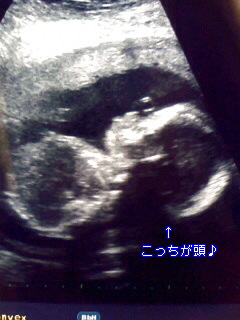

【今日の胎児の様子】 こんな感じ

(ヨメ) ねね、やっぱ、わしくんのほうに似てる感じじゃない?? てか、みんな 旦那のほうの顔は知らないか・・・。 旦那は旦那で、自分に似てるんだ と言ってるけど。でもこのおでことかアタマの形とか、お鼻のちっちゃい トコなんてどう見てもわしくんでしょ~。 ・・・・どっちにしろ、単な る親バカであることは間違いない。

・・・・ところで、この、顔の上にある丸いのってもしかして鼻風船・・・?( ̄∀ ̄;)